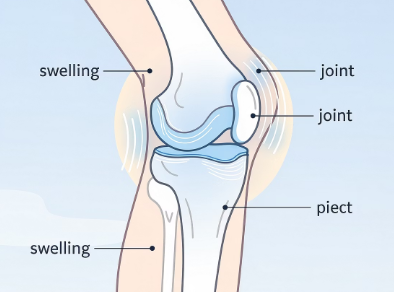

무릎에 물이 찼을 때 나타나는 증상

무릎이 눈에 띄게 붓는 느낌

무릎을 굽히거나 펼 때 불편함

압박감이나 묵직한 통증

움직일 때 뻣뻣한 느낌

열감이 동반되는 경우도 있음

증상의 정도는 원인과 염증 상태에 따라 달라집니다.